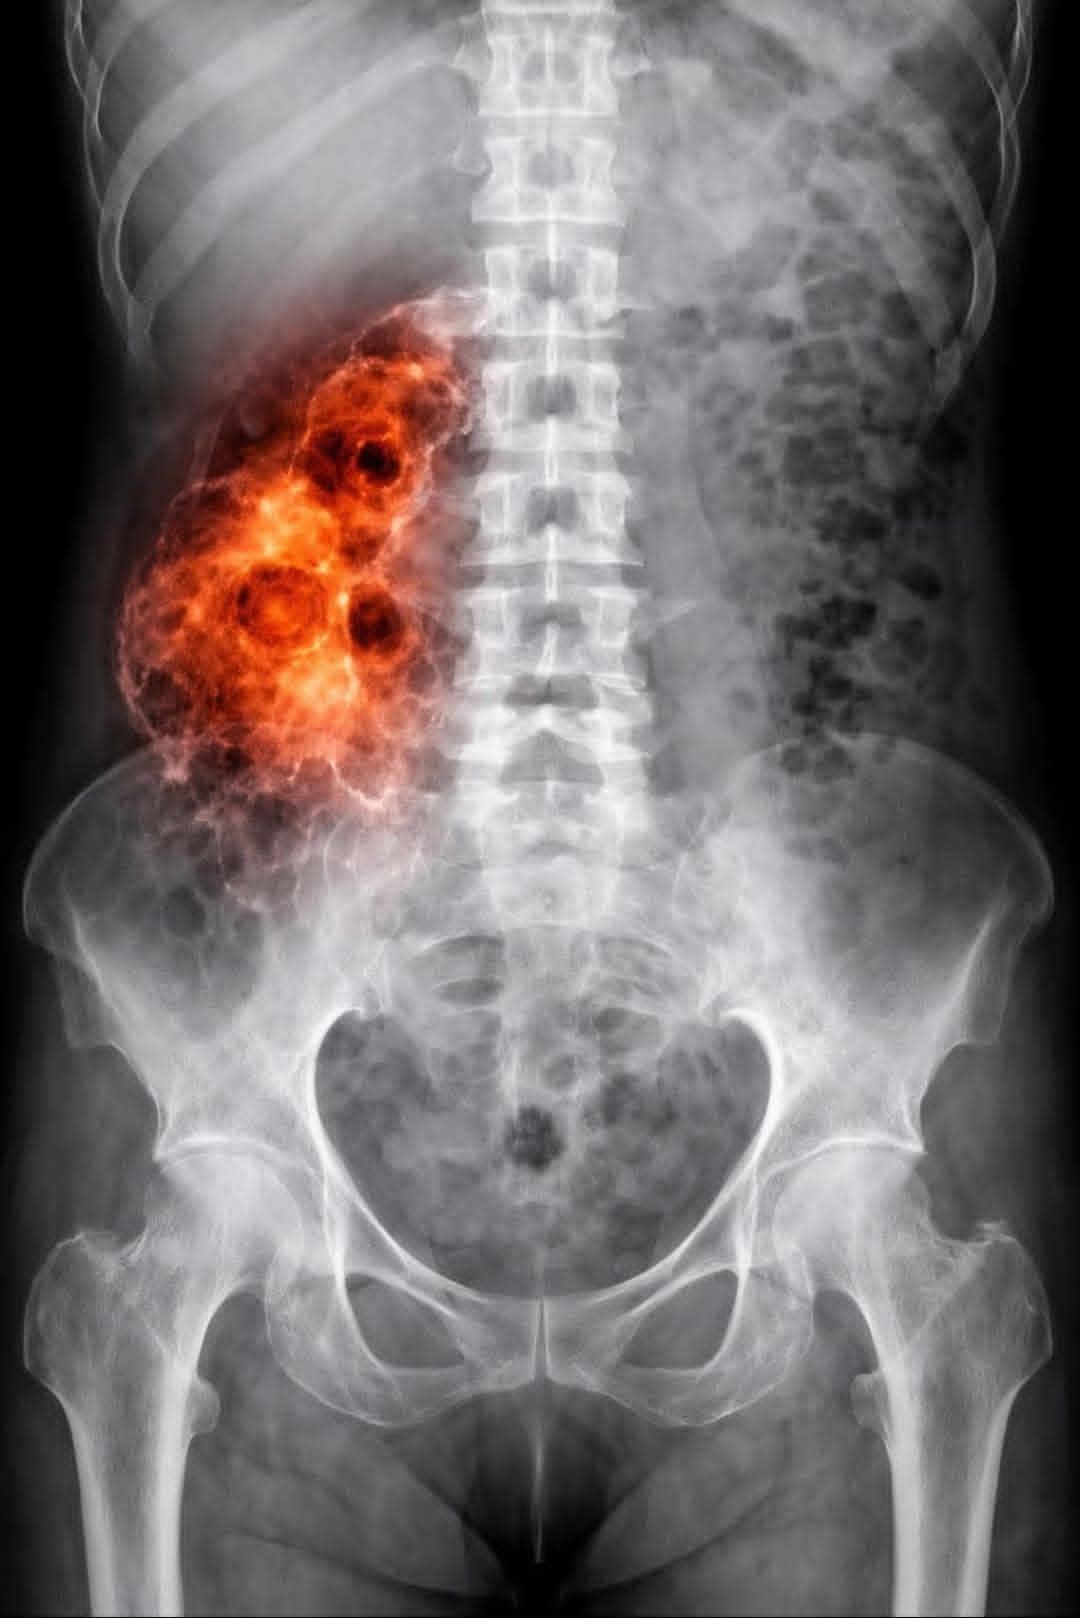

La imagen que circula en redes sociales y que encabeza esta nota es el grito desesperado de una realidad que está golpeando las puertas de los hogares mexicanos: “PENSÉ QUE ERA SOLO UN DOLOR DE CADERA HASTA QUE NADIE PODÍA EXPLICAR Po…”. Esos puntos suspensivos, mi gente, esconden un infierno que ni en las peores películas de terror se atreven a mostrar.

Ya en urgencias de un hospital de especialidades, los médicos, al ver el estado de agonía de la mujer, por fin decidieron hacer su trabajo. La metieron al tomógrafo. Y ahí, señores, fue donde el terror se hizo presente en la sala de radiología.

Las imágenes no mostraban una simple artritis, ni una hernia discal, ni el desgaste normal de la edad. Lo que vieron los doctores los dejó mudos, con la piel de gallina y sin respuestas.

El hueso de la cadera de Carmen estaba… carcomido. No había otra palabra. Parecía como si un ácido invisible lo hubiera estado disolviendo desde adentro hacia afuera durante meses. Había zonas necróticas, tejido muerto, y una inflamación que no correspondía a ninguna infección bacteriana conocida.

“El jefe de traumatología salió blanco como una hoja de papel a darnos la noticia”, recuerda Don Beto, llorando abiertamente. “Nos dijo: ‘Señor, no sabemos qué es esto. Nunca habíamos visto algo así. Parece una infección agresiva, pero los cultivos salen negativos a todo. Parece un cáncer de hueso fulminante, pero los marcadores tumorales están raros. No podemos explicar por qué su esposa se está deshaciendo por dentro'”.

La imagen viral tenía razón. PENSÓ QUE ERA SOLO UN DOLOR DE CADERA. ¡Y miren dónde terminó!